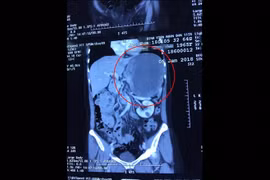

Ngày 26/4, thông tin từ Bệnh viện Chợ Rẫy TP.HCM cho biết, tại đây vừa tình cờ phát hiện một trường hợp bị khối rất lớn trong tim, nguy cơ khiến bệnh nhân đột tử bất kỳ lúc nào.